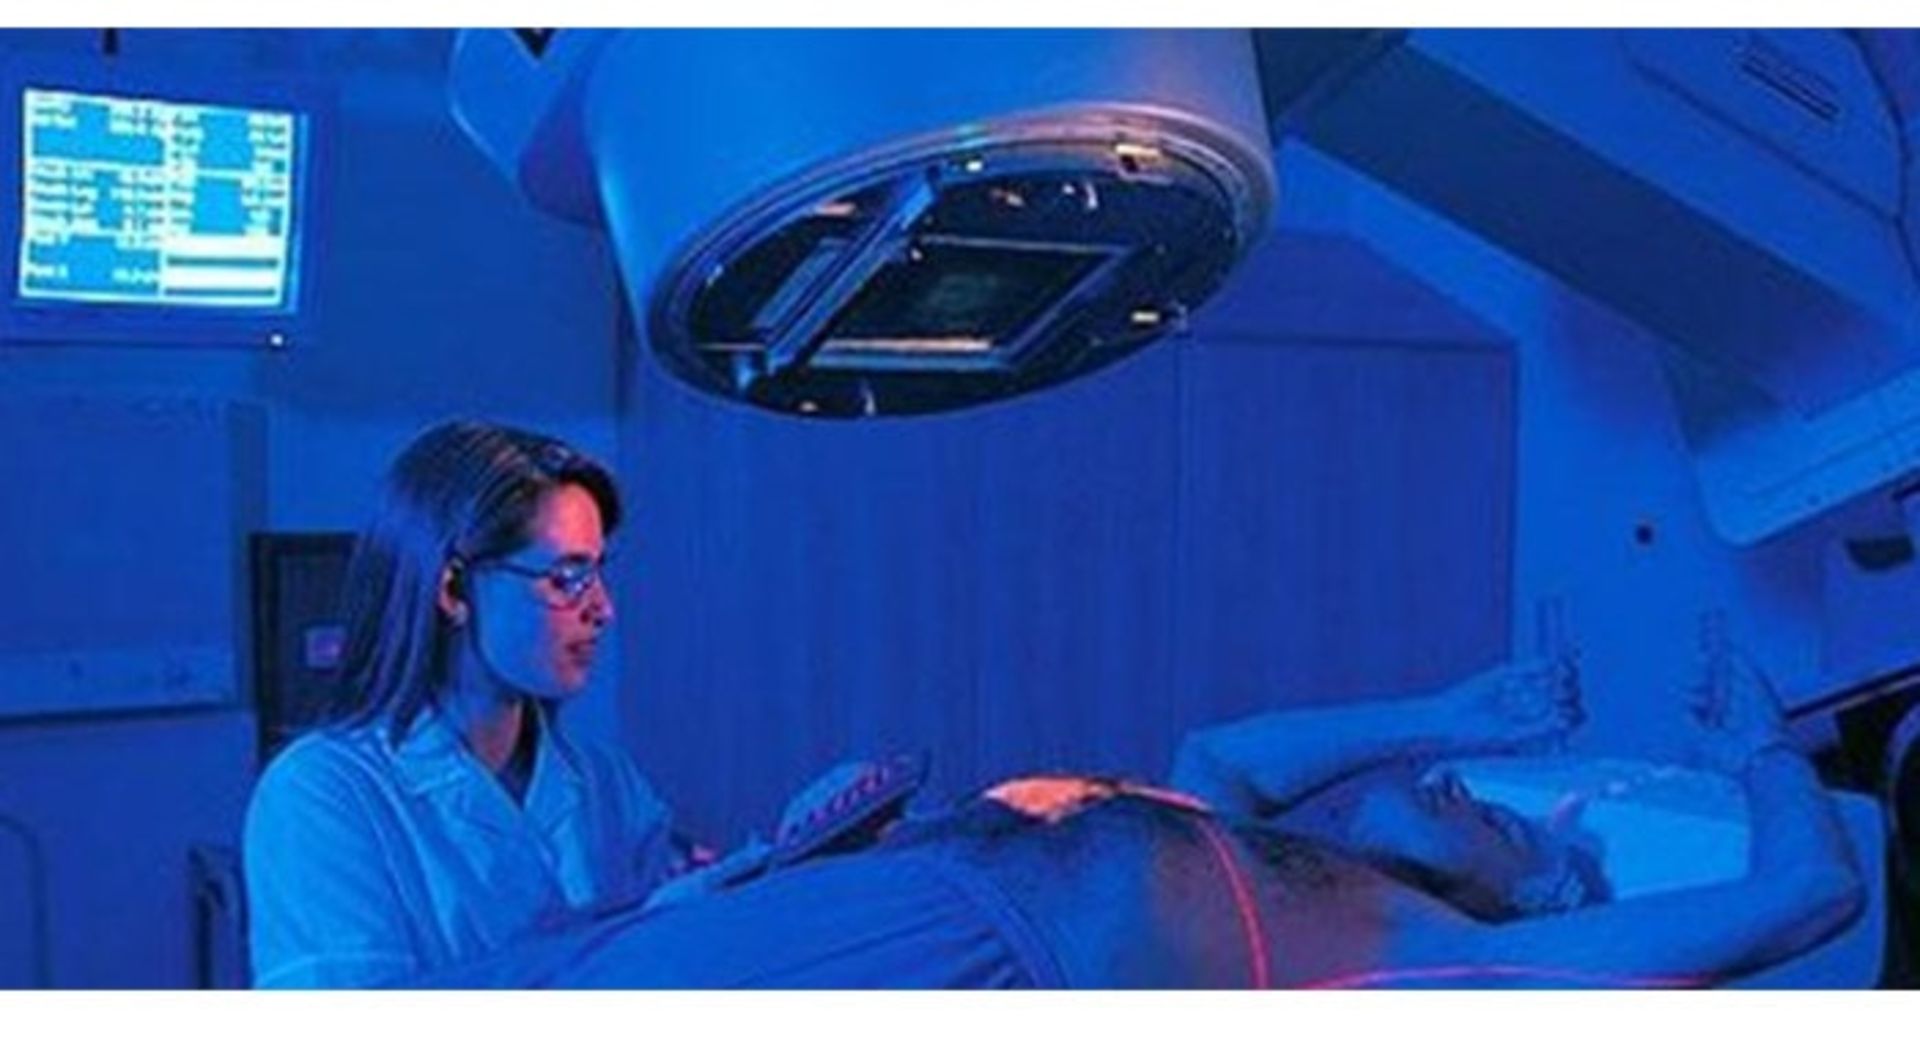

اشعهدرمانی برای سرطان معده

در اشعهدرمانی از ذرات یا اشعههای پرانرژی برای کشتن سلولهای سرطانی در یک ناحیهی خاص از بدن استفاده میشود. از اشعه به روشهای مختلفی برای کمک به درمان سرطان معده استفاده میشود:

قبل از انجام عمل جراحی برای برخی از سرطانها، اشعه میتواند همراهبا شیمیدرمانی برای کاهش اندازهی تومور و آسانتر شدن جراحی استفاده شود.

اشعهدرمانی بعد از عمل جراحی میتواند برای کشتن بقایای کوچک سرطانی که طی جراحی قابلمشاهده و برداشت نبودهاند، استفاده شود. اشعهدرمانی بهویژه وقتی در ترکیب با داروهای شیمیدرمانی نظیر ۵-FU بهکار رود، ممکن است از عود سرطان پس از جراحی ممانعت کند یا اینکه عود سرطان را به تأخیر بیندازد. از اشعهدرمانی میتوان برای کاهش رشد و توقف علایم سرطانهای معدهی پیشرفته مانند درد، خونریزی و مشکلات خوردن غذا استفاده کرد. از اشعهدرمانی خارج از بدن نیز برای درمان سرطان معده استفاده میشود. در این روش بهکمک دستگاهی که خارج از بدن قرار میگیرد، اشعههایی به بافت سرطانی داخل بدن فرستاده میشود. اثرات جانبی حاصل از اشعهدرمانی برای سرطان معده میتواند شامل موارد زیر باشد:

اشعهدرمانی همچنین ممکن است موجب بروز آسیب به اندامهای مجاور شود. این امر میتواند منجر به بروز مشکلاتی نظیر آسیب قلبی یا ریوی شود یا حتی موجب افزایش خطر بروز سرطان دیگر شود. پزشکان تا جای ممکن با استعمال دُز مورد نیاز از اشعه، کنترل محل تابش اشعهها و پوشاندن بحشهای خاصی از بدن طی درمان سعی میکنند، از بروز این مسئله پیشگیری کنند. بسیار مهم است درمان در مراکزی انجام شود که پزشکان آن در زمینهی درمان سرطان معده تجربهی کافی دارند.